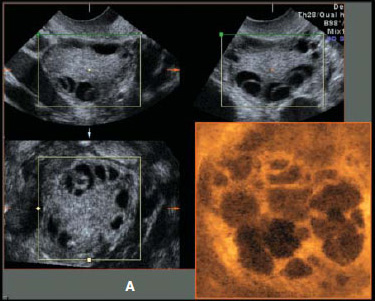

Με τον όρο πολυκυστικές ωοθήκες περιγράφουμε εκείνες τις ωοθήκες που περιέχουν πολλές μικρές κύστεις, οι οποίες συνήθως δεν ξεπερνούν τα 8 χιλιοστά σε μέγεθος, και που εντοπίζονται τις πιο πολλές φορές ακριβώς κάτω από την επιφάνεια της ωοθήκης. Οι μικρές αυτές κύστεις είναι ωοθυλάκια που περιέχουν ωάρια, λόγω όμως ορμονικών διαταραχών, τα ωοθυλάκια αυτά δεν έχουν αναπτυχθεί πλήρως και παρουσιάζουν στασιμότητα στη πορεία εξέλιξης τους. Οι πολυκυστικές ωοθήκες είναι συχνές στις γυναίκες και απαντώνται περίπου στο 20 – 30% των γυναικών

Κατά το υπερηχογράφημα σύνηθες εύρημα είναι οι πολυάριθμες μικρές κύστες περιφερειακά στην ωοθήκη. Επίσης βρίσκουμε συνήθως ένα παχύ ενδομήτριο (εσωτερική επένδυση της μήτρας) λόγω της άστατης εμμηνορρυσίας.